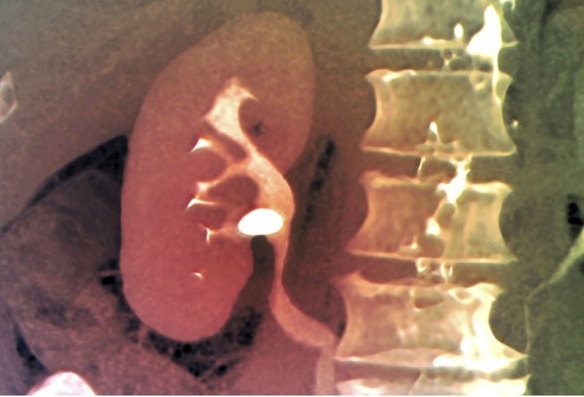

Para confirmar el diagnóstico se emplean pruebas de imagen, que nos permiten confirmar la existencia, tamaño y localización de las litiasis. La ecografía es el medio más empleado, muchas veces acompañada de radiografías con/sin contraste (urografía intravenosa o TAC). En ocasiones son necesarias analíticas complementarias o endoscopias.

Para cálculos más grandes o localizados más cerca del riñón, es necesario fragmentar primero al cálculo en pequeñas arenillas que se expulsen con la orina. Esta fragmentación puede lograrse con ondas de choque generadas por un aparato especial aplicado desde el exterior en la denominada Litotricia Extracorpórea, o bien con láser o ultrasonidos aplicados directamente sobre la litiasis dentro del organismo.